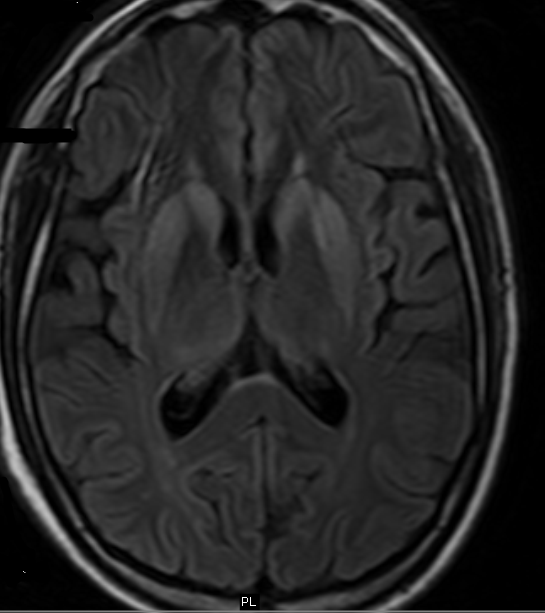

From www.pinterest.com

CreutzfeldtJakob disease (CJD) (A & B) Sporadic CJD showing hyperintense striatum on FLAIR Crutch Jacobs Disease Once symptoms start, the condition worsens quickly, causing a. It affects the brain and causes dementia and other. A brain biopsy or an exam of brain tissue after death, known as an autopsy, is the gold standard to confirm the presence of creutzfeldt. Also called classic cjd, it worsens quickly. Crutch Jacobs Disease.